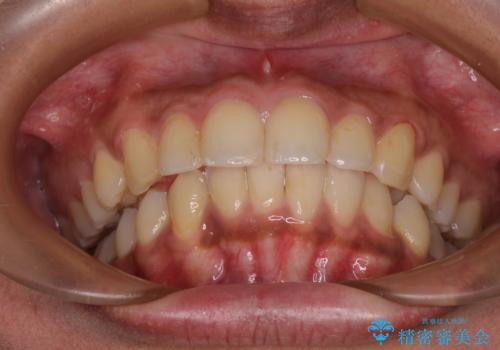

深い咬み合わせと前歯のデコボコ インビザラインによる矯正治療

治療途中では、左右ともに奥歯が咬みにくい状態が続き、問題なく噛めるようになるまでに長期間を要しました。

一方で、デコボコや下顎の前歯が隠れてしまうほどの深い咬み合わせはしっかりと改善されました。